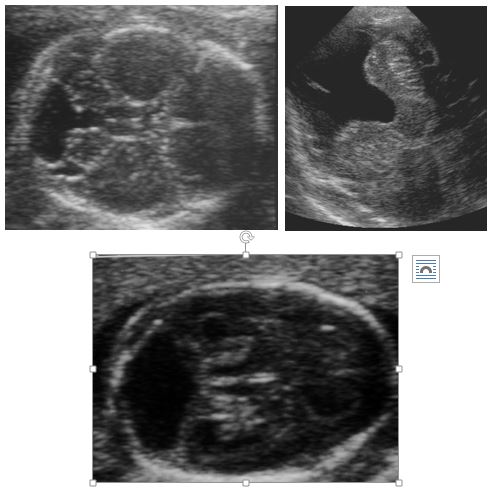

If you can’t find a cisterna magna to even measure (i.e. it is completely effaced) then you are most likely dealing with a Chiari malformation. This shape of the cerebellum is referred to as the banana sign. You can see that in the picture below (Figure 4.4), the cerebellum looks is banana shaped and there is no discernible cisterna magna. Unfortunately, it is not always this pretty, so if you are having trouble even seeing the cisterna magna, you should be suspicious. Of course, Chiari malformations are also associated with ventriculomegaly and a distal spinal dysraphism.

Figure 4.4. There is not visible cisterna magna. The cerebellum has a “banana” configuration, consistent with a Chiari malformation and should prompt a detailed evaluation of the distal spine for a myelomeningocele.

Figure 4.5. The still image in Figure 4.4 shows a near perfect “banana sign” but often times, when there is a Chiari malformation, due to the small cisterna magna, crowding of the cerebellum and shadowing from the bones, it is difficult to see well. Thus, you must maintain a high index of suspicion if you are not able to get a good view of the cisterna magna.